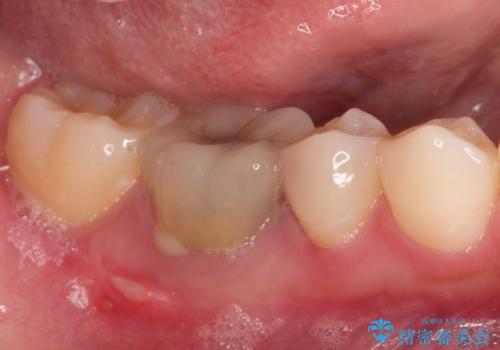

- 費用(概算)

- 約40万円(インプラント部のみ)費用は治療当時の料金となります